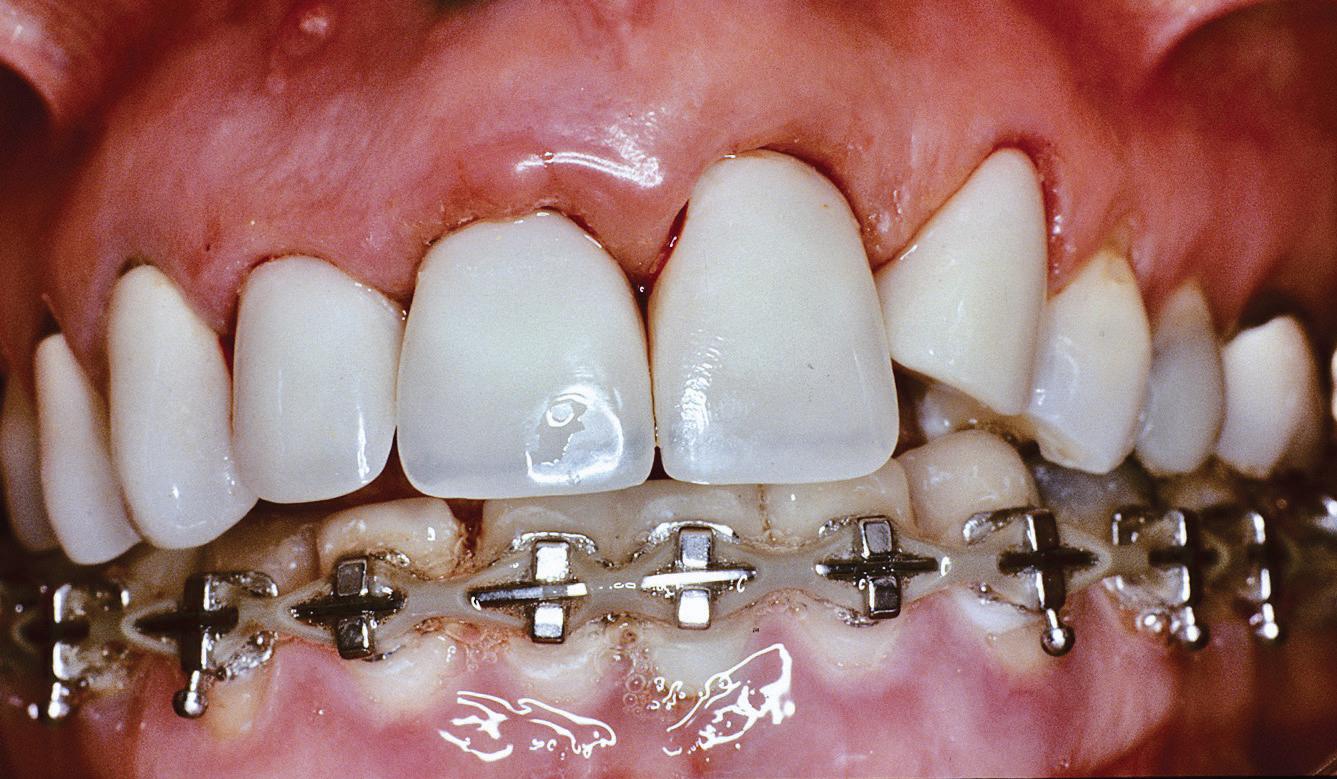

Lamboul repoziționat apical

Această tehnică este o opțiune atunci când nu există suficient țesut gingival keratinizat și este preferată atunci când caninul impactat este situat mezial față de incisivul lateral. Lamboul trebuie fixat și adaptat la dinte. Dezavantajele includ riscul de recesie și marginea gingivală neregulată, alături de necesitatea unei intervenții chirurgicale osoase extinse. Se efectuează incizii verticale, iar lamboul este deplasat într-o direcție laterală sau apicală. Se recomandă un design al lamboului în care baza și zona coronară sunt fie la aceeași lățime, fie mai înguste la bază, cu o grosime de 4-5 mm, astfel încât lamboul să fie suficient de lat meziodistal, extinzându-se cu 1,5 mm dincolo de unghiul dintelui (fig. 6, 7).

Osul acoperitor trebuie îndepărtat cu chiuretă sau freză diamantată pentru a expune porțiunea liberă a coroanei. Lamboul se poziționează apoi la CEJ și se fixează cu suturi periostale pentru o stabilitate mai mare. În funcție de gradul de impactare a caninului, se poate plasa un pansament parodontal, astfel încât țesutul să nu se închidă. Bracketul este plasat fie în momentul procedurii, fie la 10 zile postoperator. Dacă respectivul canin este situat prea apical, se preferă tehnica închi-

să. În general, deplasarea ortodontică începe la 4-6 săptămâni după expunerea chirurgicală. Când foliculul ce înconjoară caninul este larg, incizia lamboului trebuie făcută peste limitele acestuia, pentru a permite adaptarea optimă a lamboului la coroană și os. Pentru a determina buna adaptare a lamboului, atunci când buza se mobilizează, acesta ar trebui să rămână staționar.

6, 7. Utilizarea lamboului repoziționat apical pentru a gestiona caninii bilaterali cu impactare facială. După expunere, s-a practicat și frenectomia și au fost plasate bracketuri bilaterale (fig. 6). S-a realizat tracțiunea ortodontică, ce a permis poziționarea corespunzătoare a ambilor canini pe arcada superioară (fig. 7)